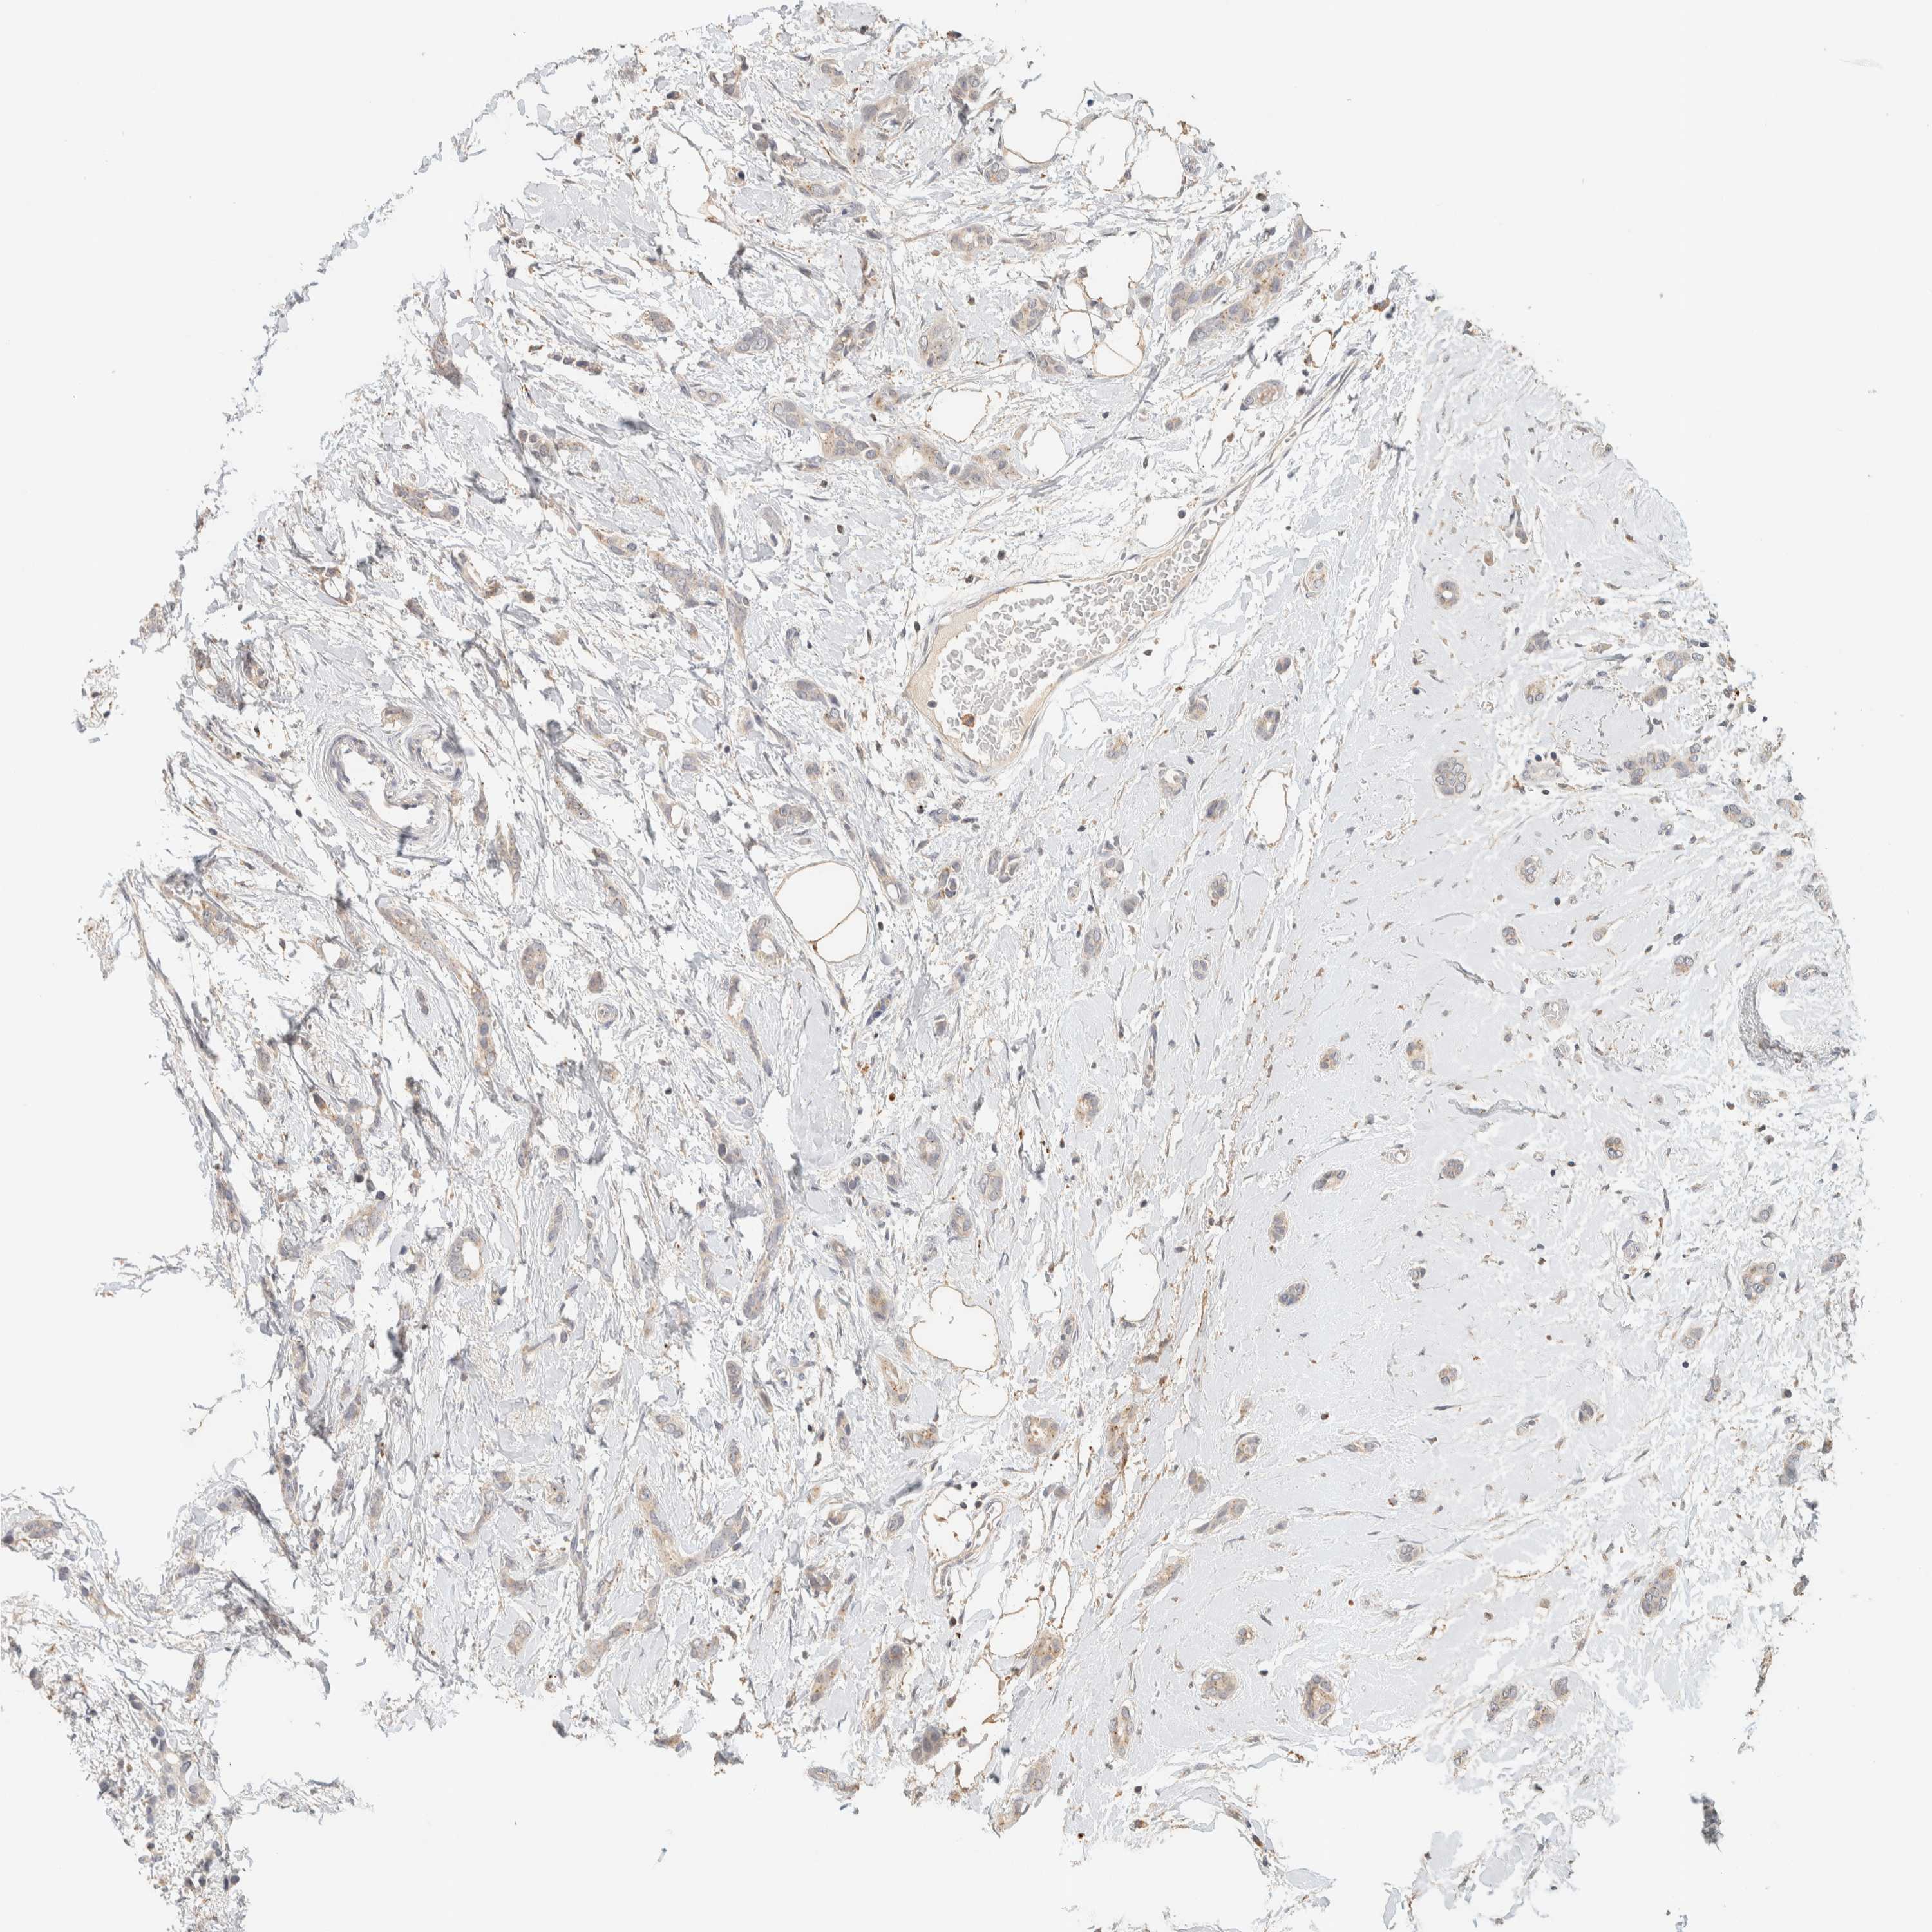

CANCER BREAST CANCER Show tissue menu

BRCA TCGA BRCA VALIDATION PROTEIN EXPRESSION

ANTIBODIES

AND

VALIDATION